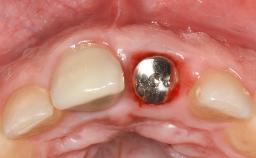

Late Presentation of Peri-Implant Mucositis Requiring Soft-Tissue Augmentation and Esthetic Crown Lengthening at Implant Site 11